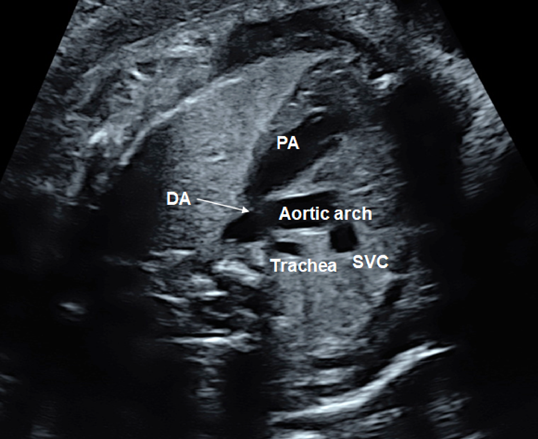

(5) Three-Vessel Trachea View

The 3VTV is obtained by translocating the probe parallelly from the 3VV plane to the cranial aspect of the fetus (Fig. 12). The superior vena cava, the trachea, the aortic arch, and the ductal arch are observed; in this order from the right to the left. The left aortic arch normally runs along the left side of the trachea, and the aortic arch and the ductal arch merge together on the dorsal side, forming a V-shape there. Either the aortic arch or the ductus arteriosus has anterograde blood flow. Some abnormalities can be recognized in the 3VTV.

1. Significant Differences in Diameters of the Aortic Arch and the Ductal Arch

Diameters of the aortic arch and the ductal arch are typically similar. When the aortic arch is narrow, aortic coarctation or interrupted aortic arch should be suspected.

2. Absence of a Unilateral Arterial Arch

In fetuses with pulmonary atresia without central pulmonary arteries or in those with persistent truncus arteriosus, the ductal arch is not found in its normal position. Only the aortic arch is to be seen. When the aortic arch is interrupted, in contrast, the ductal arch forms a solitary arch without connection to the ascending aorta. In fetuses with transposition of the great arteries, both arterial arches are present with the ascending aorta in front of the pulmonary trunk. The V-shaped connection is, therefore, not shown in a single horizontal plane, but a long aorta appears in the antero-posterior view (I-shaped sign).56)

3. Abnormal Direction of Blood Flow across the Arterial Arches

Blood flow across the ductal arch is retrograde in fetuses with stenotic lesions of the right heart, such as pulmonary atresia. Blood flow through the aortic arch is retrograde in fetuses with obstruction of the left heart, such as hypoplastic left heart syndrome. Premature constriction of the ductus arteriosus is to be suspected when the ductus arteriosus blood flow cannot be seen in the normal range of velocity or when the distal end of the ductus arteriosus is not connected to the aortic arch, irrespective of the size of the ductus arteriosus.

4. The Aortic Arch along the Right Side of the Trachea

When the aortic arch is found along the right side of the trachea with the ductal arch found on the the left of the trachea, it is likely vascular ring. Without detecting the left-sided arch structure, it is probably a solitary and right-sided aortic arch.